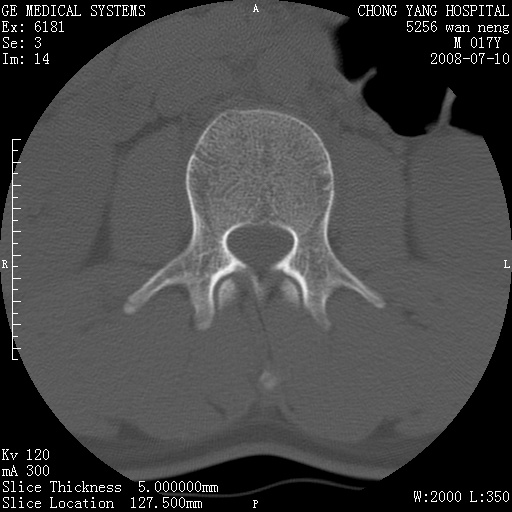

腰3、4椎弓崩裂

腰3、4椎弓不连

支持:腰3、4椎弓峡部崩裂。

腰3、4椎弓峡部不连

支持:腰3、4椎弓峡部崩解。

腰3、4,如受过外伤则为陈旧骨折,否则为骨质不连

图片漂亮,目前也只能看到腰3、4骨质不连

腰3、4椎弓峡部裂。

腰3、4椎弓峡部裂。支持

重建图像见多个椎弓峡部不连(不足为据),平扫未见异常。

支持腰3、4椎弓峡部崩裂。